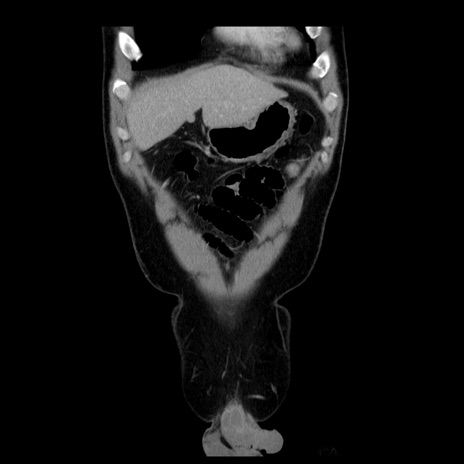

症例4(冠状断像)

【症例】30歳代男性

【主訴】腹痛、嘔吐

【現病歴】昨晩から突然の腹痛あり、その後嘔吐、軟便も出現。腹痛が改善しないため救急搬送となる。2日前にしめ鯖の食事歴あり。

【身体所見】意識清明、苦悶様、BP 135/90mmHg、BT 35.7℃、腹部:平坦、やや硬、心窩部〜臍部に自発痛、圧痛あり、筋性防御+、反跳痛-

【データ】WBC 8100、CRP 0.57